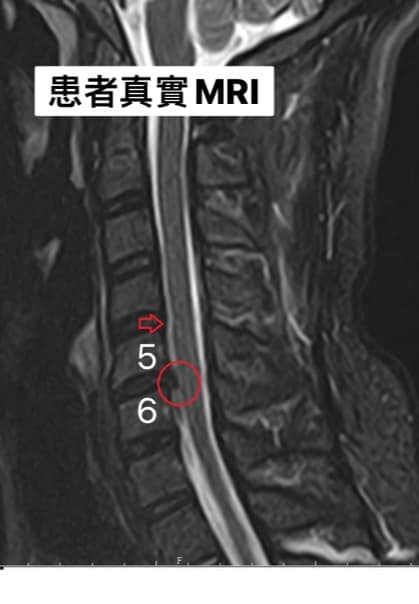

Cervical Spine Treatment Cases 頸椎治療案例 頸椎壓迫竟導致自律神經失調?耳鳴、心悸、暴瘦全因筋膜失衡! 2021.02.18 頸椎壓迫神經根導致工作受限?非手術微創療法改善關鍵公開 2021.02.17 頸椎脊髓壓迫五大症狀公開!你也有雙腳沉重、手腳麻電感嗎? 2021.01.15 長期頭痛吃藥沒效?小心你可能是「頸源性頭痛」患者 2021.01.07 #感謝新北市蘆洲區楊先生熱情見證 #頸椎病變引起肩膀痠痛無法睡眠 #曾經大痛到想立刻... 2020.12.31 #感謝新北三重劉小姐熱情見證 #神經根型頸椎病經典案例 #曾經手麻痛到無法騎摩托車 #... 2020.12.25 #遠從台東縣的熱情見證 #五個多小時的車程三百多公里很辛苦 #疼痛超過兩年打過頸椎三... 2020.12.24 #頸椎酸痛到無法睡覺是怎們回事 #醫學中心證實頸椎間盤突出 #神外醫師建議開刀但患者... 2020.12.19 #頸椎曲線弧度非常重要 #頸椎嚴重壓迫有可能逆轉嗎 #肩膀疼痛到不行合併走路都無力 #... 2020.12.09 頸椎退化壓迫神經根怎麼辦?大直林小姐四週見效的中醫微創療法 2020.12.08 #特殊案例長年過敏性鼻炎 #起因居然是頸椎交感神經筋膜壓迫 #打開椎動脈循環🔄找到解... 2020.12.05 #恭喜新店陳小姐頸椎療程畢業 #神經根型卡壓醫案 #頸椎整合中醫微創療法逆轉勝 #告別... 2020.11.24 #特殊案例頸椎手術後又再度突出案例 #感謝台中劉大哥熱情見證 #親自手捏醫師娃娃公仔... 2020.11.18 #頸椎病居然會導致手快速萎縮 #脊髓型頸椎病案例 #感謝高雄王大哥熱情見證 #頸椎整合... 2020.11.13 #神經根型頸椎病讓人痛到無法入眠 #感謝新店陳小姐熱情見證 #患者的疼痛日誌讓人感動 ... 2020.11.11 ← 上一頁 3 4 5 6 7 下一頁 →